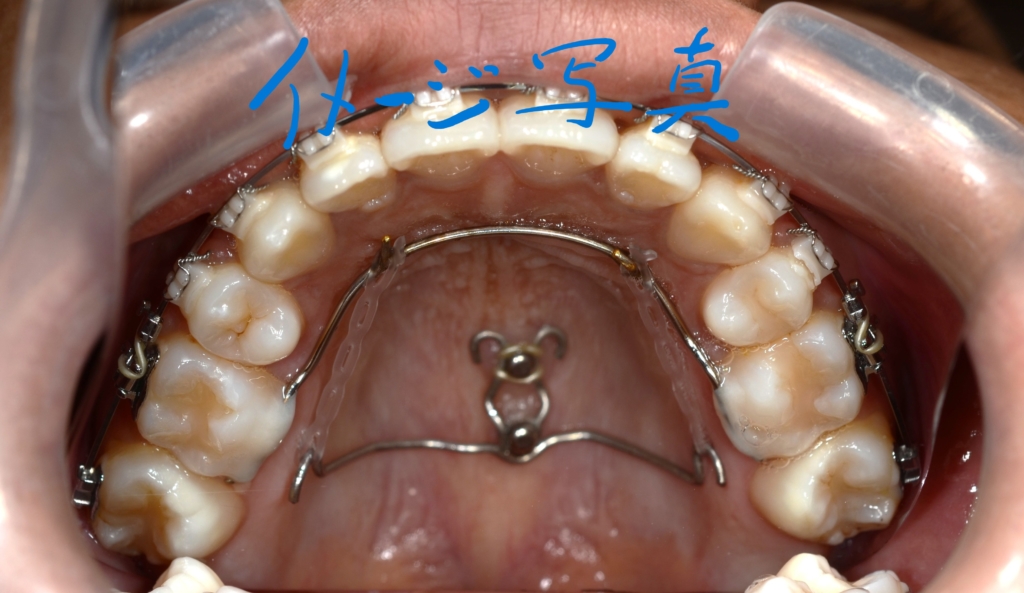

上顎のアンカースクリューには、PLAS & 奥歯の内側にはパラタルバーを付けて

下顎のアンカースクリューには、よじったワイヤーフックを付けて

上下の歯列(歯並び全体)を出来るだけ後方へ引っ込めて行く「矯正力」を加えて、治療を再開しました。

スイマセン・・・

この方の写真を探したのですが見つからないため、全く同じことをしている患者さんの写真を「イメージ写真」として代用しています。